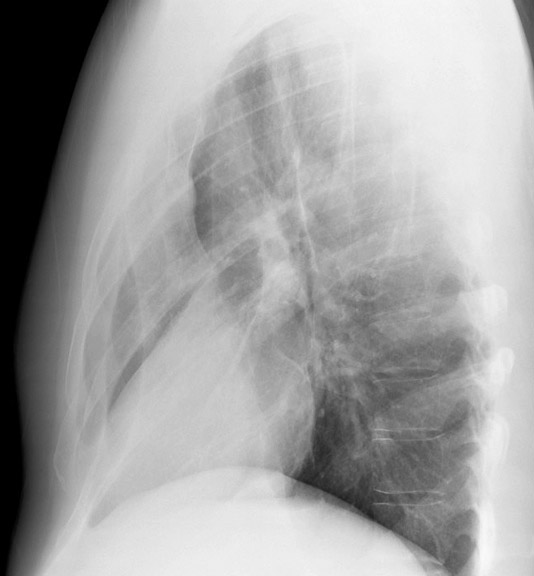

Gallery Lobar Collapse RML Collapse Case 2 Lateral

Case 2 Lateral